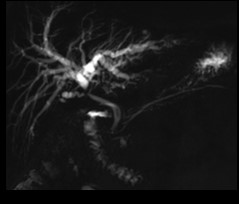

- Voie biliaire

Voie biliaire